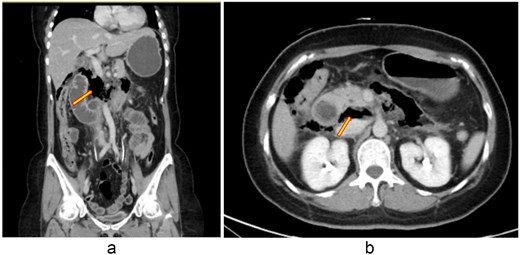

A 48-year-old woman with adenomyosis and prior gynecologic surgeries was diagnosed with influenza A at a local hospital on 21 August 2025. On 26 August, she presented with 4 days of diffuse abdominal pain, fever, chills, and nausea. Computed tomography (CT) revealed intra-abdominal free air, suggesting hollow organ perforation (Fig. 1). Retrospective review of the initial CT demonstrated subtle indirect findings, including retroperitoneal fat stranding and mild wall thickening of the third portion of the duodenum, without definite localization of the perforation. She received intravenous piperacillin–tazobactam and underwent emergency surgery.

(a, b) Contrast-enhanced abdominal CT scan (26 August 2025). Imaging demonstrates retroperitoneal free air with suspicion of perforation in the retroperitoneal region.